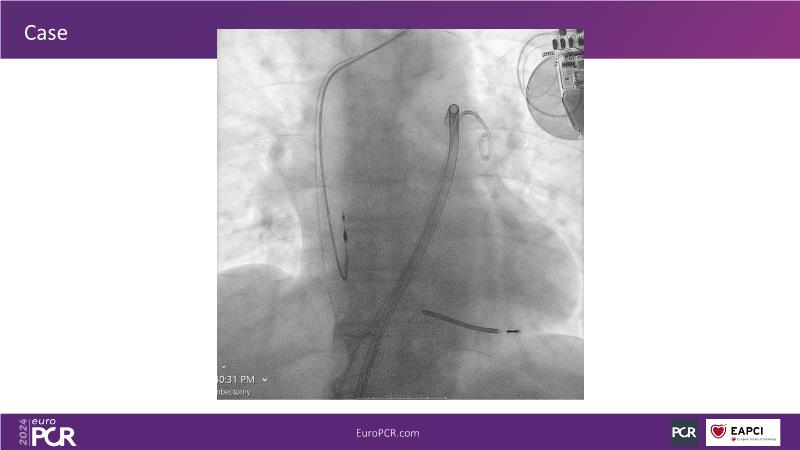

Advancing percutaneous treatment of pulmonary embolism with computer-assisted vacuum thrombectomy

Join this session to delve into innovations in computer-assisted vacuum thrombectomy for acute pulmonary embolism, leveraging real-life case scenarios to share practical experiences and discuss treatment strategies. Amidst the current surge in scientific research, ongoing trials like STORM PE and STRIKE PE are pivotal in shaping the landscape of pulmonary embolism management.